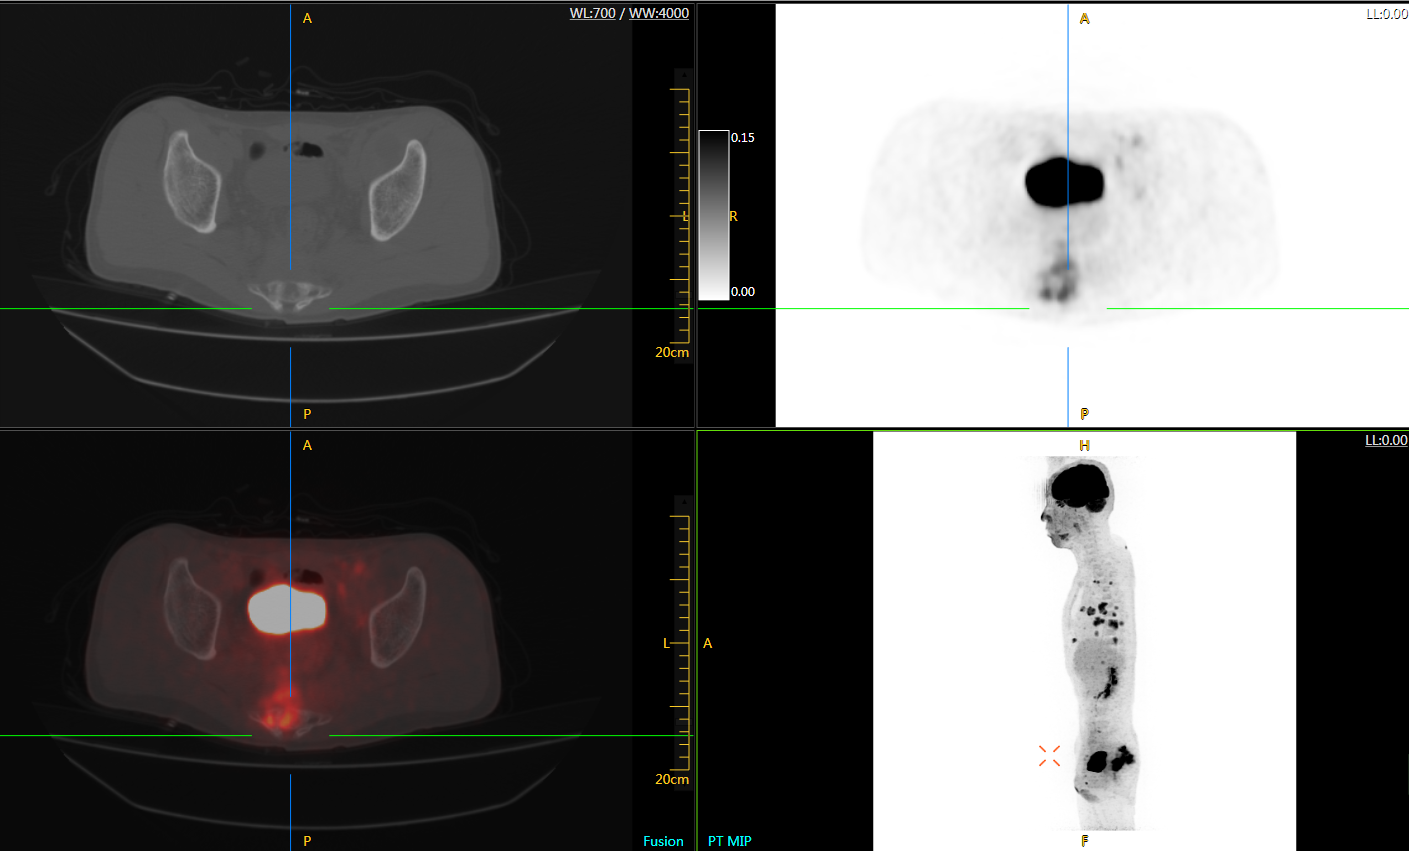

肺癌轉(zhuǎn)移及復(fù)發(fā)

患者男性,66歲,七年前發(fā)現(xiàn)右肺肺癌,其間手術(shù)兩次,共切除兩個(gè)肺葉,復(fù)查;

診斷意見,回腸轉(zhuǎn)移,右肺殘留部復(fù)發(fā)